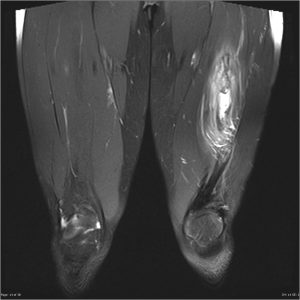

Диагностика, основанная на исследовании мягких тканей: УЗИ, МРТ и исключении переломов — рентгенограмма.